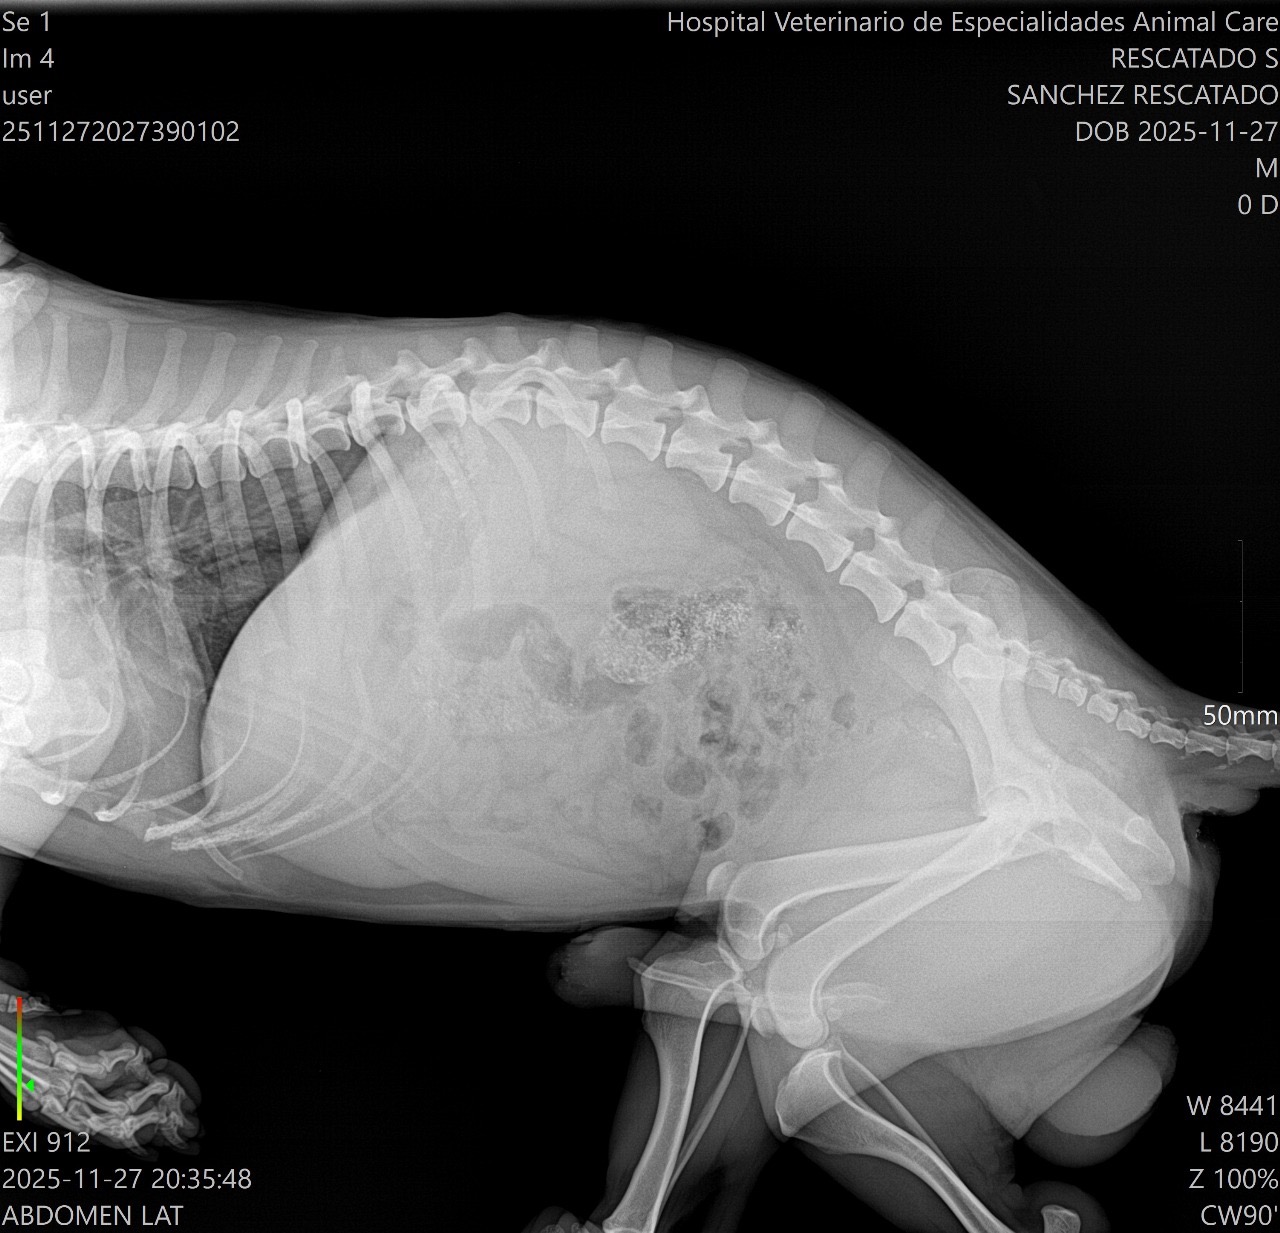

to the local vet who did X-rays, blood work and an ultrasound. This poor baby has two pelvic fractures, one sacroiliac fracture, one hip fracture one ischium fracture and a rib fracture he is also heartworm positive. We were referred to a surgeon in a different state for a consult, today we drove him to the surgeon who miraculously confirmed there is no internal bleeding, his bladder and liver are intact, his lung was not punctured by the rib and the ultrasound revealed no mature worms in his heart or arteries. He will be able to make a full recovery with surgery and treatment. Unfortunately logistics aren’t working in our favour. The surgeon is not confident doing repairs of the pelvis and won’t perform the surgery on his hip for another month then there is another month of recovery before he would be cleared to fly. The costs to board the dog at the vet awaiting the surgery and for the recovery, the medication, the cost of additional flights and the cost of the surgery itself quickly add up to nearly the same costs of treatment in Canada. Matt and I we are already $1000 deep trying to save this little guy who we’ve lovingly named Squeegee after we squeegeed this little pancake off the road. We are hoping to raise funds to bring this little guy home with us for treatment in Canada on Dec 4th. I have been in touch with our regular vet who has confirmed these injuries require surgery. The anticipated costs will range from $4000-8000. Anything you are willing to contribute will help, we will cover the rest. In the event there were excess funds not used for his care we would donate to an animal rescue in Mexico that helps other street pups like Squeegee.